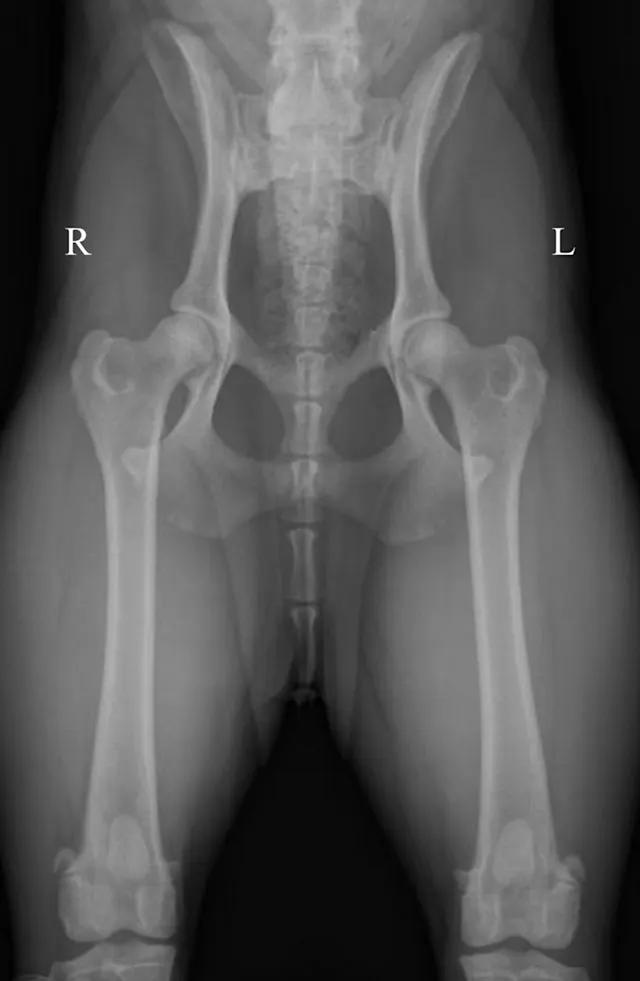

Figure 1A demonstrates the normal positioning for the ventrodorsal hip-extended view (the view that should be submitted to the Orthopedic Foundation for Animals). This view is best obtained with the dog placed in dorsal recumbency, which is done by using a foam positioning trough. All but the pelvis and hindlimbs are within the trough. While in a flexed position, the limbs are internally rotated and abducted so that the stifles are almost touching. The limbs are then extended, maintaining the internal rotation, until the femurs are parallel with the table.

If the stifles are kept internally rotated, the patella should be centrally located over the distal femurs, as seen in the normally positioned radiograph (Figure 1B). In this image the femurs are parallel with each other and parallel with the imaging plate. Note the uniform and equal size of the obturator foramen on this well-positioned radiograph. Ideally, the sacrum, ilial wings, and entire 7th lumbar vertebra should be included in the image. Figure 1C shows an example of the pelvis correctly positioned.